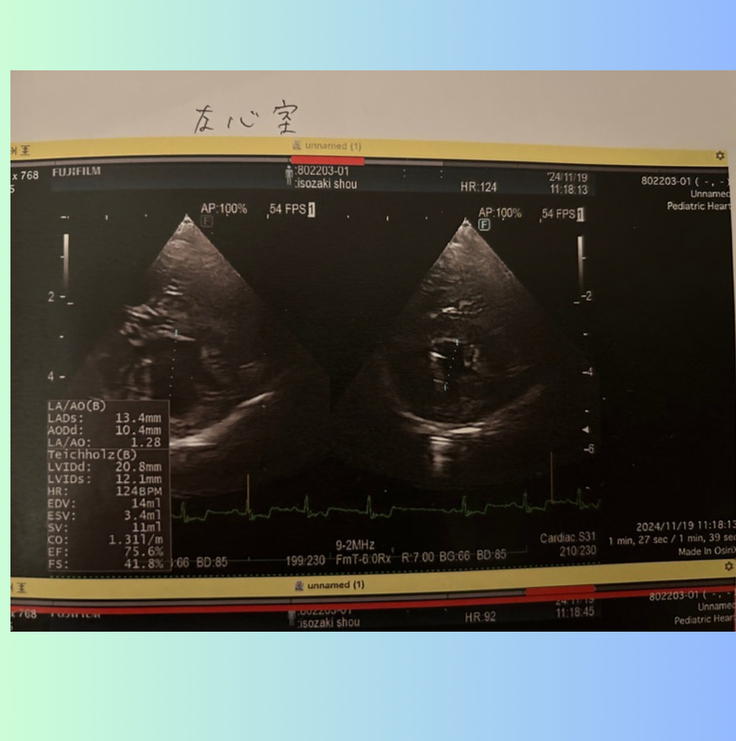

左心房の大きさは....

手術前は、2.5倍に肥大していましたが、

2ヶ月検診では、1.28まで小さくなっていました。